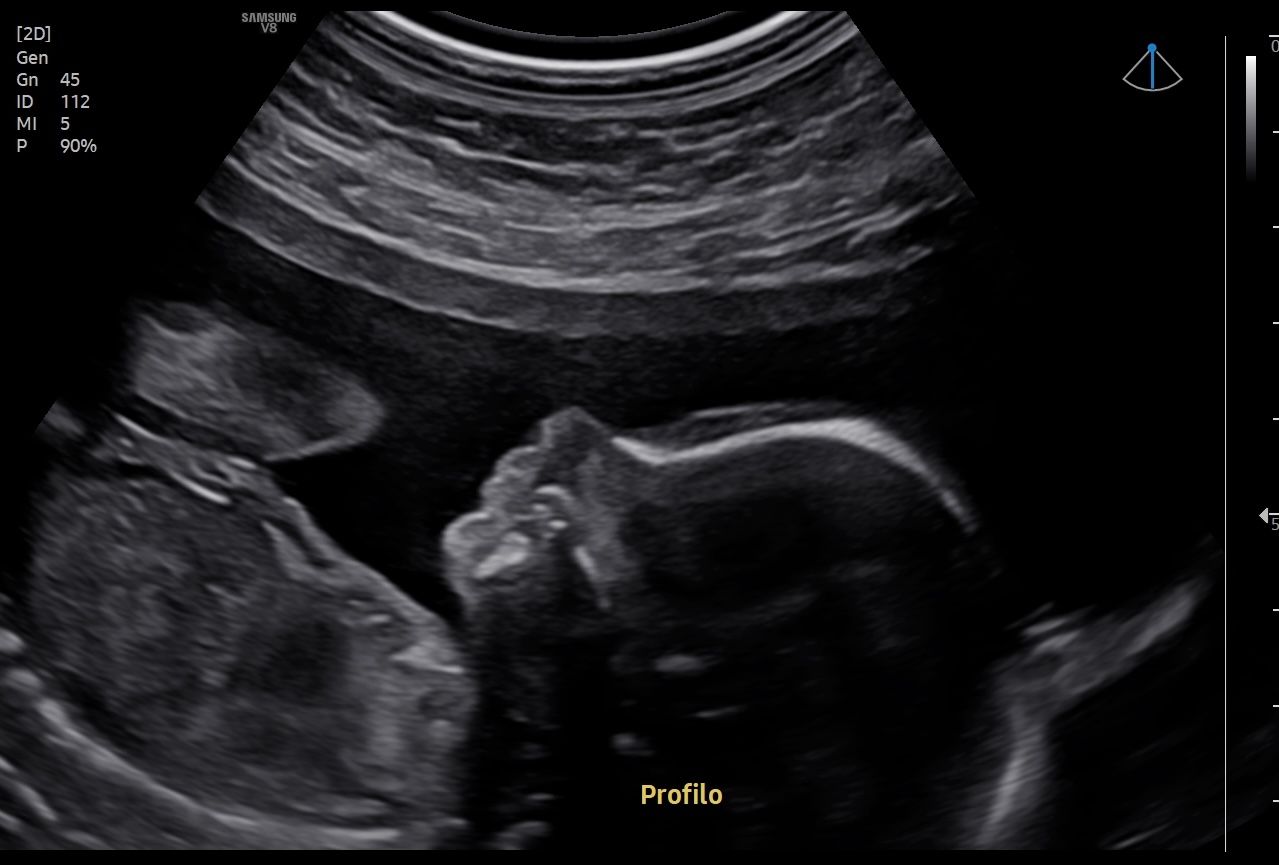

• Visita ed ecografie in gravidanza

• Ecografia Ostetrica con studio della Traslucenza Nucale

• Ecografia Morfologica e Premorfologica

• Ecografia Ostetrica 3D/4D con Flussimetria materno-fetale